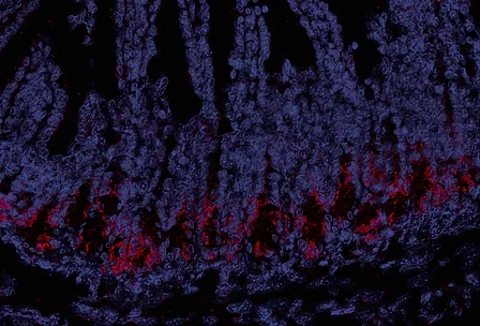

Eine mögliche Komplikation bei der Stammzelltransplantation ist die Graft-versus-Host-Reaktion (GvHD), bei der Immunzellen aus den transplantierten Zellen entstehen. Der Schlüssel, um dies zu verhindern liegt im Darm.